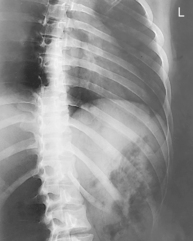

The routine for a sternum generally includes a lateral and an oblique wherein the sternum is shifted to the left of the spine and is superimposed over the homogeneous heart shadow. A 15°–20° RAO achieves this best. An orthostatic-breathing technique generally is used to blur out the lung markings and the ribs overlying the sternum. If preferred, exposure can also be made on suspended expiration.

Rotate thorax 10°–15° to shift vertebrae away from sternum (best visualizes downside SC joint). RAO will demonstrate the right SC joint. LAO will demonstrate the left SC joint.

Less obliquity (5°–10°) will best visualize the upside SC joint next to spine.